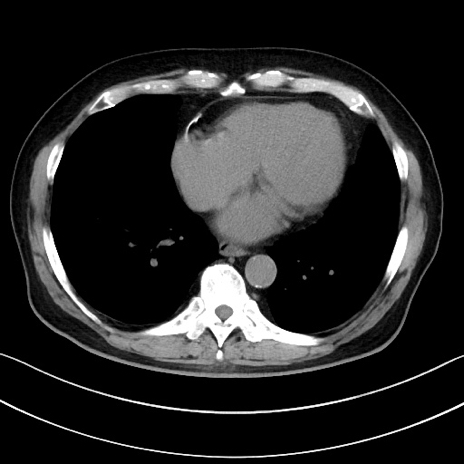

症例15(横断像)

【症例】70歳代男性

【主訴】腹痛

【現病歴】今朝から腹痛あり。全体的に痛い。特に左上の方。排ガスが今日はない。冷や汗が出る。

【既往歴】直腸癌術後

【身体所見】左側腹部〜上腹部に圧痛あり。腹膜刺激症状明らかなではない。軽度反跳痛。左下腹部に術後瘢痕あり。

【データ】WBC 7700、CRP 0.02